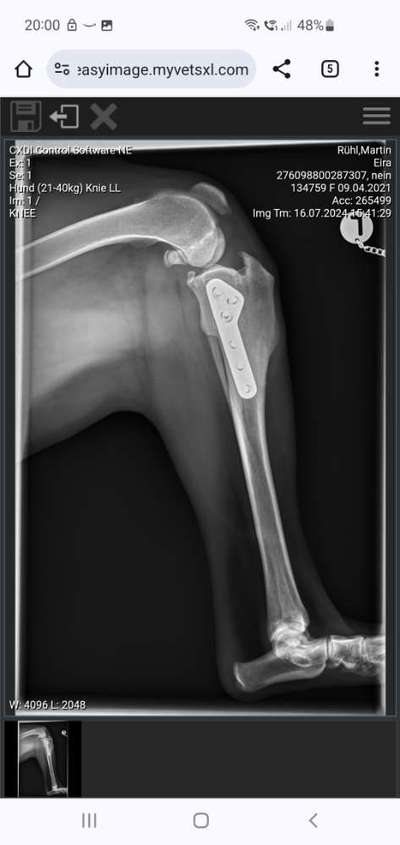

Und bumms war es am 31.5. wieder so weit: Kreuzbandriss Nummer 2. Wieder in Grußendorf, aber dieses Mal ganz anderer, viel besserer Wund- und Heilungsverlauf. Dann 6 Wochen strikte Einhaltung der Regeln, inklusive 2x die Woche Physio. Kurze Leine , am Anfang 5 bis 10 min Kurzspaziergang mehrmals am Tag. Nach vier Wochen auf 15 bis 20min immer noch an der Kurzleine. Auch der Physio war von den Fortschritten angetan. Gestern nach 6 Wochen Kontrollröntgen und alles ist verheilt. Nun noch mal vier Wochen Leistungssteigerung schrittweise, dann Freigabe für alles. Seit gestern an der 10m Leine und heute zum ersten Mal wieder kontrolliert mit Abrufsignal 10m gerannt. Was für eine Freude! Somit jetzt stetig steigern und freuen.. Lg Martin

Nach 6 Wochen Kontrollröntgen.